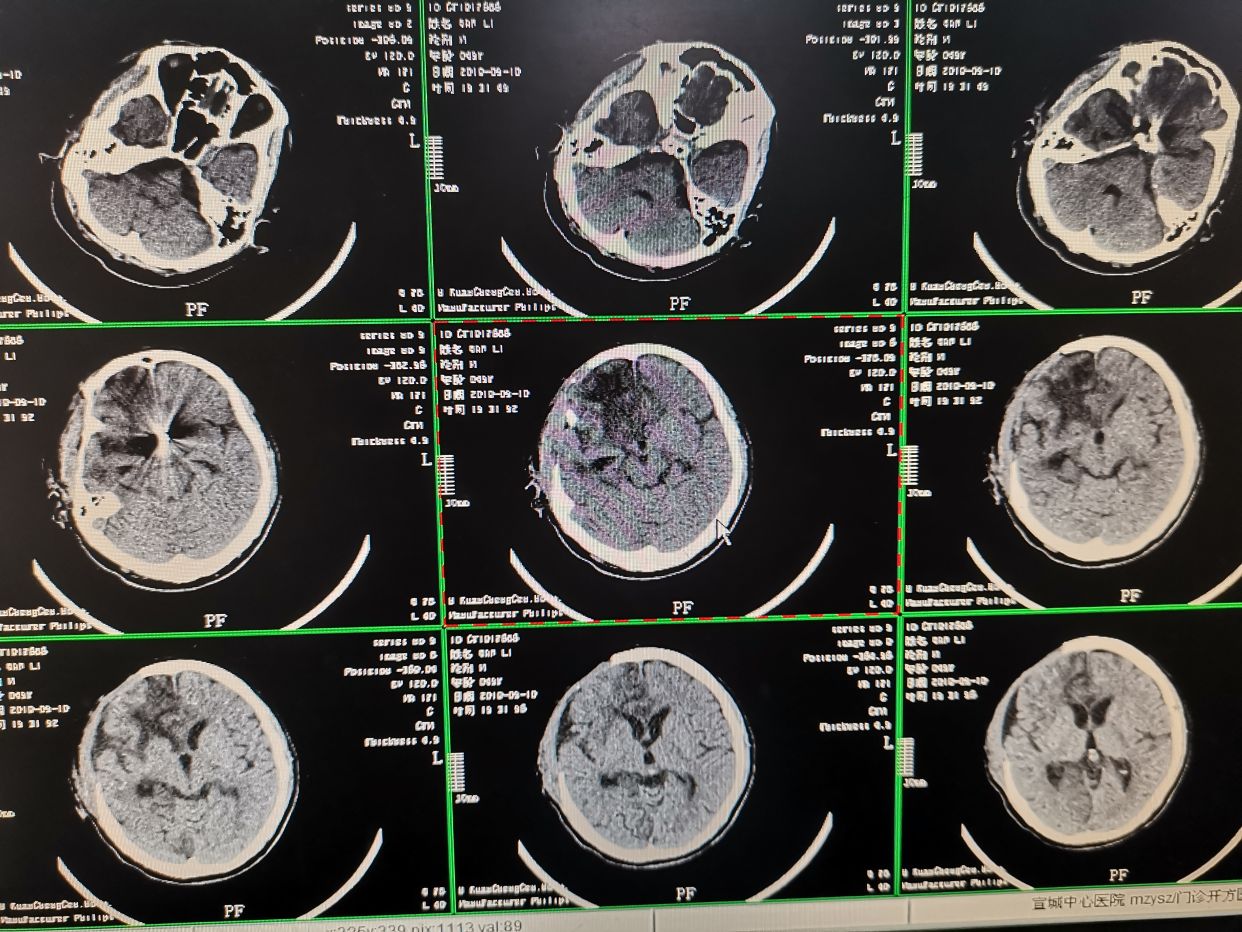

入院CT提示蛛网膜下出血,右额叶出血。

入院CT检查

造影结束。患者全麻状态,观察患者瞳孔,右侧瞳孔散大,对光反射消失。立即行CT检查发现右额叶脑内血肿较前明显增加,脑内血肿形成。相关病情告知家属。拟立即快速行弹簧圈填塞术,术后直接入手术室行右侧开颅脑内血肿清楚术+去骨瓣减压术。

术后即刻CT。术后给予对症支持治疗。